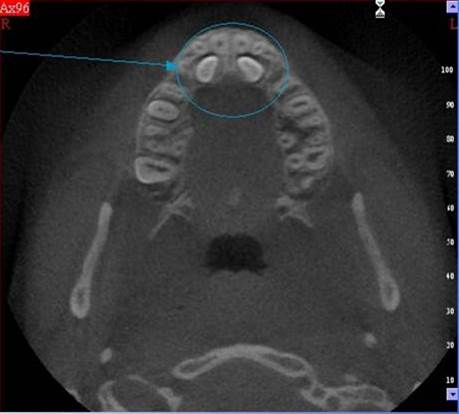

Je speciální zubní digitální tříprostorový tomograf (3D), který umožňuje na základě jediného snímkování vytvořit všechny typy RTG zobrazení, které jsou pro lékaře potřebné. Díky používané technologii tzv. „kuželového paprsku“ a speciálním senzorům je výrazně zmenšená dávka záření - o více jak 80% proti klasickému CT vyšetření. To je významné zejména u dětí. Pomocí tohoto přístroje je možné zjisti skutečnou situaci v čelistních kostech pacienta tedy množství kosti - můžeme změřit skutečnou šířku i výšku kosti, i kvalitu kosti (hustotu) v místě uvažované implantace. 3D (tříprostorové) zobrazení umožňuje zvýšit prostorovou představu operatéra ještě před vlastní operací a zároveň pacientovi lépe objasnit a ukázat oblast plánovaného zavedení implantátu.

Pacient „neumí číst“ RTG snímky, ale díky 3D zobrazení vidí „svoji skutečnou čelist“ - např. jak je nízká či úzká, vidí průběh nervu nebo velikost čelistní dutiny, což mu umožní i pochopení nutnosti v některých případech provést pomocné zákroky ještě před vlastním zavedením implantátu (viz. kostní štěp, sinus lift, kostní granulát...).

Vyšetření pomocí tohoto přístroje používáme i ve stomatochirurgii (zlomeniny čelistí, zuby moudrosti, cysty, onemocnění čelistního kloubu), ortodoncii (retinované zuby, nadpočetné zuby), parodontologii atd.